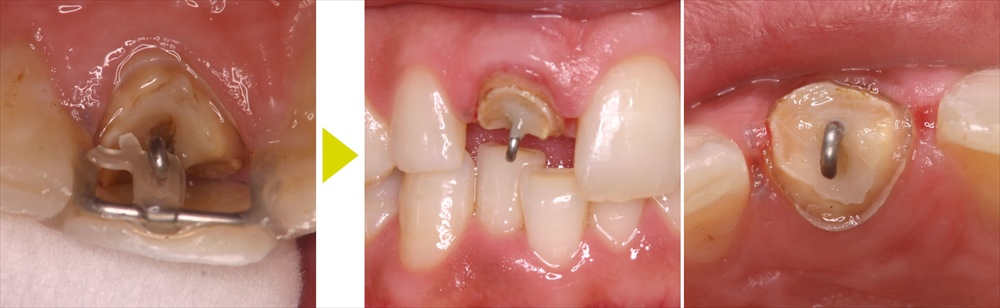

差し歯が土台ごと取れて、 支えていた歯も 折れてしまいました。このようなケースでは周りの歯肉より下まで歯がないので、このままでは新しい歯を作ることができず抜歯になる事がほとんどです。

この歯をなんとか残して治療するには、周りの歯肉や骨を削って歯を出すか、矯正で引っ張って歯を出すかどちらかを選択しなければなりません。前歯の目立つ部分で歯肉や骨を削ってしまうと、見た目が悪くなってしまうので、今回は矯正で引っ張り出す治療を選択しました。

両サイドの歯を固定源として、ゴムの力で歯を骨から引っ張り出して治療が出来る状態にしました(エクストルージョン)。

エクストルージョン中の正面からの見た目の写真ですが、牽引していることがわかりません。治療後は、エクストルージョンによって引っ張り上げた歯根に土台を形成し、そのうえにセラミックの歯を装着し治療完了となります。